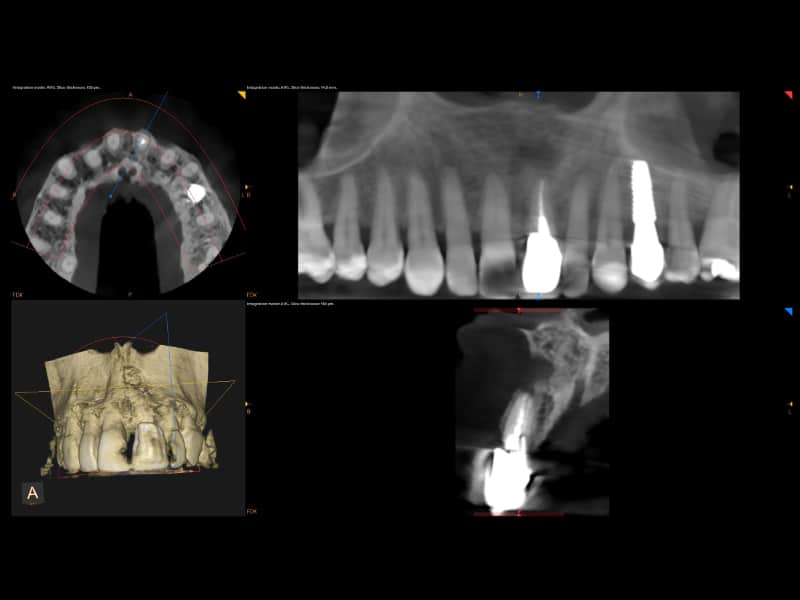

Dentalna dijagnostika

Marković Dental Clinic koristi najmoderniju rendgensku tehnologiju u dijagnostici orofacijalne regije. Uz minimalnu dozu zračenja pacijenata i maksimalnu zaštitu, rendgenskim snimkama čeljusti možemo analizirati anatomske osobitosti zuba, čeljusti, patološke procese i tvorbe te visinu i širinu kosti čeljusti za planiranje dentalnih implantata.